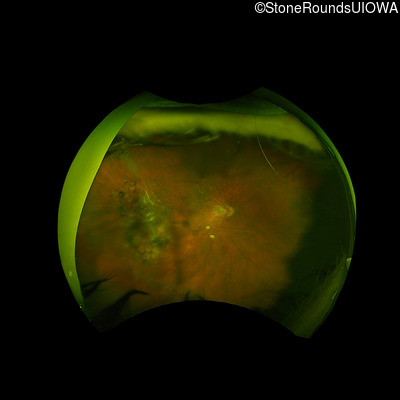

AD Familial Exudative Vitreoretinopathy (IIIE2b)

Age at visit: 32 years

This 32 year old woman has had subnormal acuity (right eye worse than left eye) since very early childhood.

Diagnosis & molecular findings

AD Familial Exudative Vitreoretinopathy TSPAN12 Arg50Trp AG(G)>TG(G)   AD